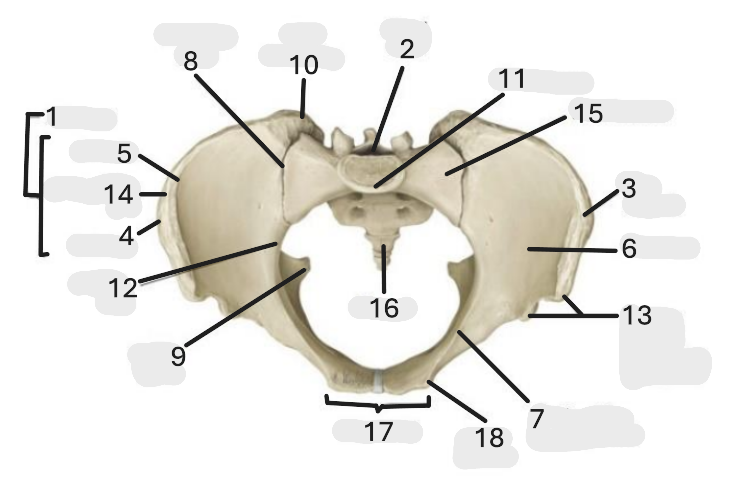

Where is the pelvic inlet

1

Where is the sacro-iliac joint

2

Where is the pubic tubercle

3

Where are the S1 body

4

Where is the ischial spine

5

Where is the ala of sacrum

6

Where is the anterior superior iliac spine

7

Where is the ischiopubic ramus

8

Where is the coccyx

9

Where is the obturator foramen

10

Where is the pubic symphysis

11

Where is the ischial tuberosity

12